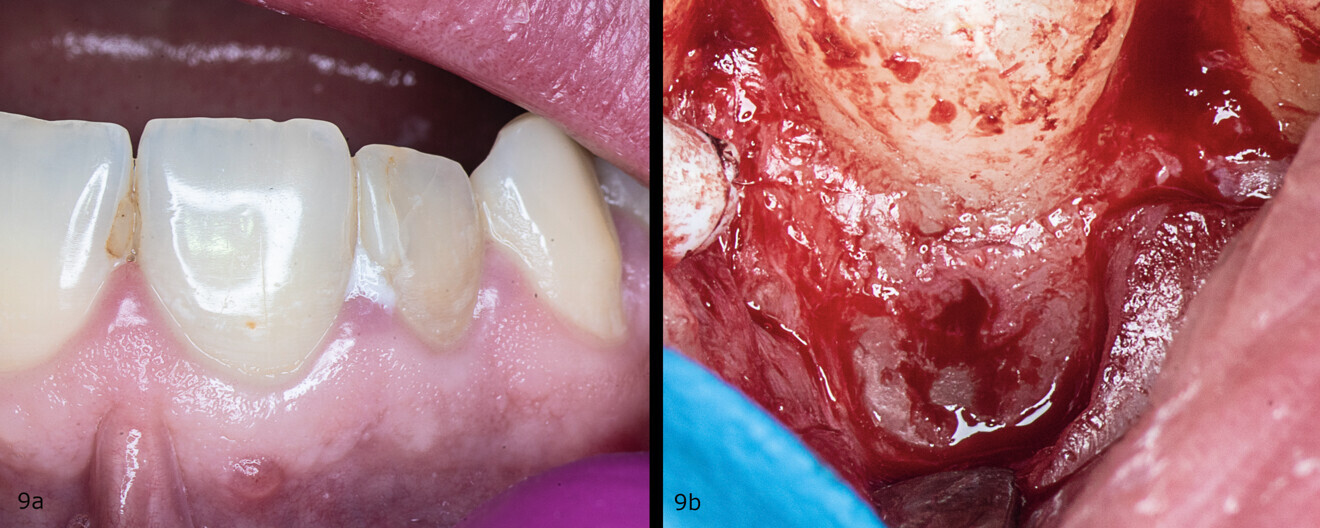

A 28-year-old patient was referred to the endodontic office after diagnosis of inflammatory IRR in the maxillary right central incisor on a periapical radiograph. A CBCT scan was taken to determine the prognosis and to plan the treatment (Figs. 8a-e). The 3D image revealed perforation of the labial wall of the root and destruction of the bundle bone surrounding the resorption cavity.

Figs. 9a & b: Clinical situation before the procedure (a) and after raising of the flap and perforation of the cortical bone (b).

An incision was made from the maxillary left central incisor through the gingival sulcus to the right maxillary canine. After raising a flap, the granulation tissue was removed from the resorption cavity with a small excavator (Figs. 9–11). The root canal shaping protocol was performed with conventional chemomechanical preparation. The shaping sequence began with negotiation with passive hand files, followed by preparation with rotary files and irrigation using sodium hypochlorite with manual needle agitation. The irrigation protocol was performed as described in Case 1.